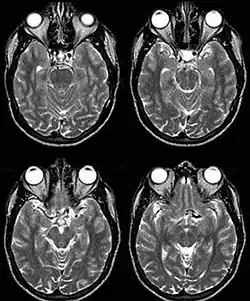

Internal carotid artery dolichoectasia is particularly interesting because the artery normally already contains one hairpin turn. Seen in an MRI as two individual arteries at this hairpin, a carotid artery dolichoectasia can progress so far as to produce a second hairpin turn and appear as three individual arteries on an MRI. In the case of a dolichoectasia of the Internal Carotid Artery (ICD), the pathogenesis is primarily related to compression of the optic nerves at the optic chiasma (see Fig. 1 and 2).